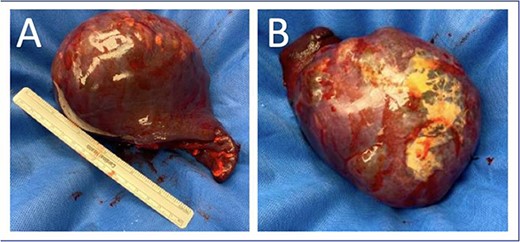

He was taken to the operating room and underwent an upper midline laparotomy. After inspection of the abdominal cavity and confirmation of no additional peritoneal lesions or significant adhesions to the spleen, the splenic vessels were controlled with 0-silk ties. The spleen was then mobilized and removed without violation of the splenic capsule and the abdomen closed (Fig. 2). He had an uncomplicated post-operative course and was discharged to home on post-operative Day 1.

Splenectomy specimen with intact capsule with underlying cystic structure. (A) Anterior surface; (B) Posterior surface.

Pathology revealed an 18.0 × 4.0 × 11.0 cm3 spleen weighing 855 g, with a 10.5 cm in greatest dimension cyst occupying 75% of the splenic surface. Sections revealed a multilocular cyst with copious cloudy yellow fluid and trabeculated walls. Immunohistochemical staining of the cyst wall was positive for cytokeratin (AE1/AE3) consistent with a benign multilocular mesothelial cyst without malignancy.